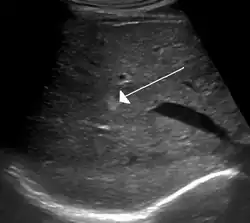

On ultrasound, cavernous haemangiomas in liver appear as homogenous, hyperechoic lesions with posterior acoustic enhancement. On CT or MRI scans, it shows peripheral globular/nodular enhancement in the arterial phase, with portions of attenuation of enhancing areas. In the portal venous phase, it shows progressive centripetal enhancement. In delayed phase, it shows retention of contrast. It shows a high signal on T2 weighted images.[24]